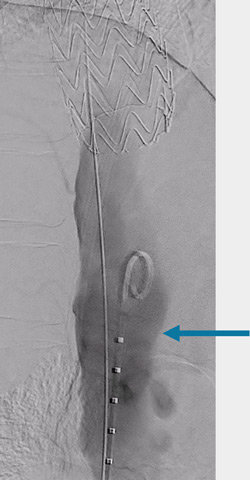

Step 1

GORE® TAG® Thoracic Branch Endoprosthesis (TBE)

Challenging branch take-offs may require specific angulations!

Step 1: result